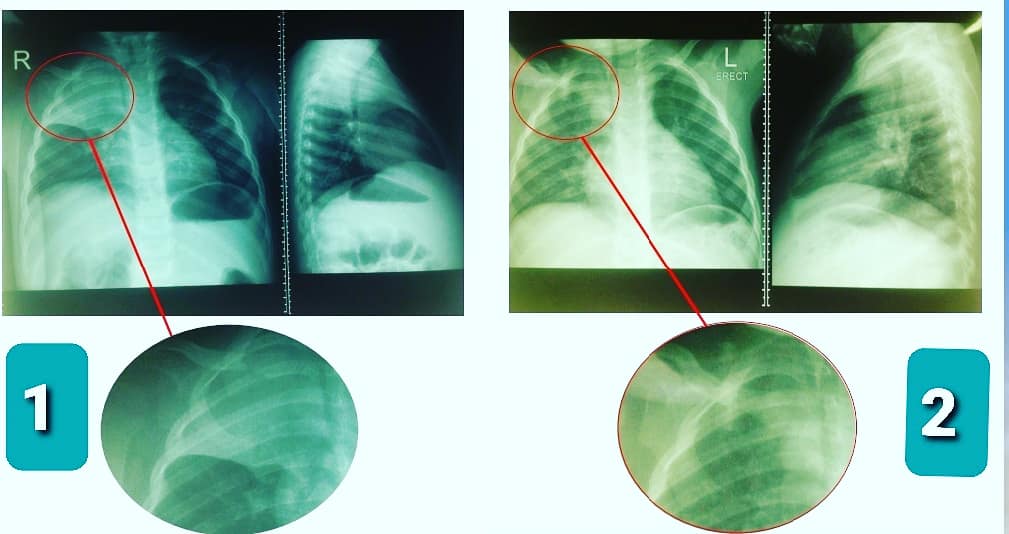

Споделяме резултат на наш пациент:

Подобно на многобройните мнения, получени от колеги в чужбина, гореспоменатите изследвания документират следните резултати: